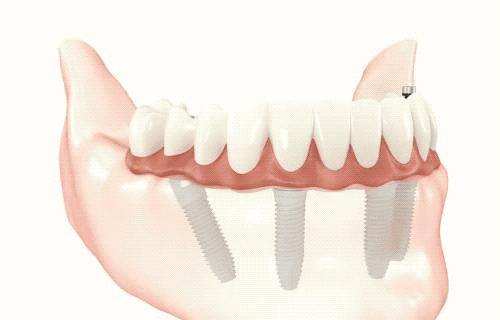

种植牙就是在我们缺失牙齿的区域,将种植体(人工牙根)植入骨头内,几个月后,种植体与牙槽骨完成紧密骨结合,能在骨头内能够稳固生存,再在种植体的上面接上烤瓷牙恢复牙齿的形态和功能。所以,种植牙就是用种植体代替天然牙根、烤瓷牙恢复牙冠的一种牙齿缺失的修复方法,可以获得与天然牙功能、结构以及美观效果。

5.适应症更广:在全口均无牙齿或磨牙区后部全部缺失的情况下,以往只能装活动假牙,但活动假牙在美观、舒适、咀嚼功能、自洁能力等各方面均不尽如人意,而通过人工牙根的植入就可以使这些患者获得固定义齿修复。